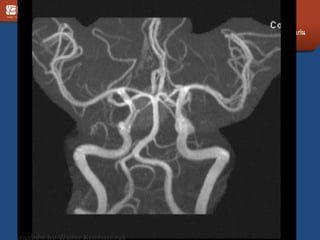

Carotid artery

• Aneurysm

• Ectasia

• Anomalies